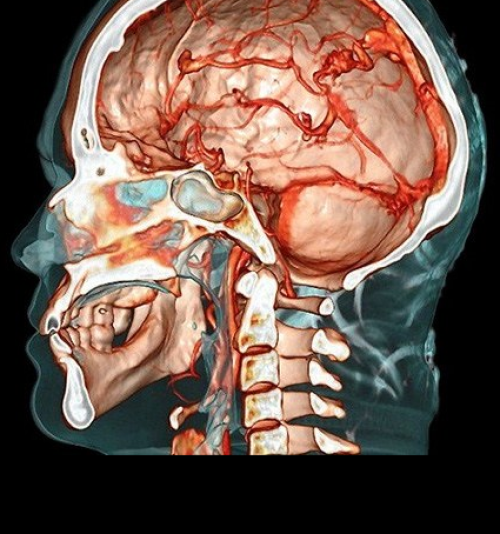

NEUROCIÊNCIAS

O curso de pós-graduação em Neurociências, tem como objetivo formar especialistas capazes de integrar conhecimento avançado em Neurociências com aplicações práticas em ciências do comportamento, abrangendo desde aspectos básicos do comportamento humano até fenômenos sociais complexos.